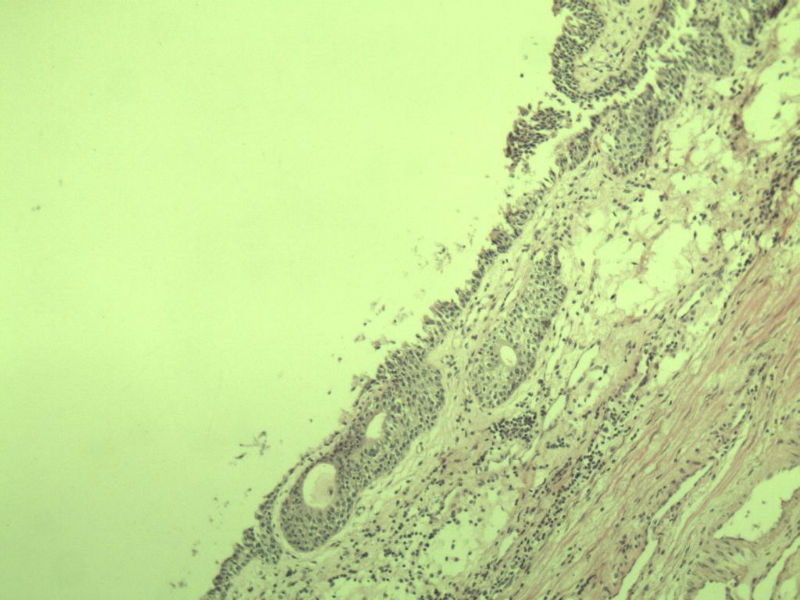

男 75岁 因排尿困难半年行前列腺切除术,体积 4 × 3 × 2.5 cm3,切面灰白,实性,质韧。请各位老师看看 有问题没? 谢谢了!

前列腺增生症伴鳞化

良性前列腺增生

良性前列腺增生伴尿路上皮化生

呈巢上皮为尿道周围前列腺组织正常现象。尿路上皮-前列腺腺体过度。

良性。

前列腺增生伴尿路上皮鳞化及Brown巢形成,未见恶性。